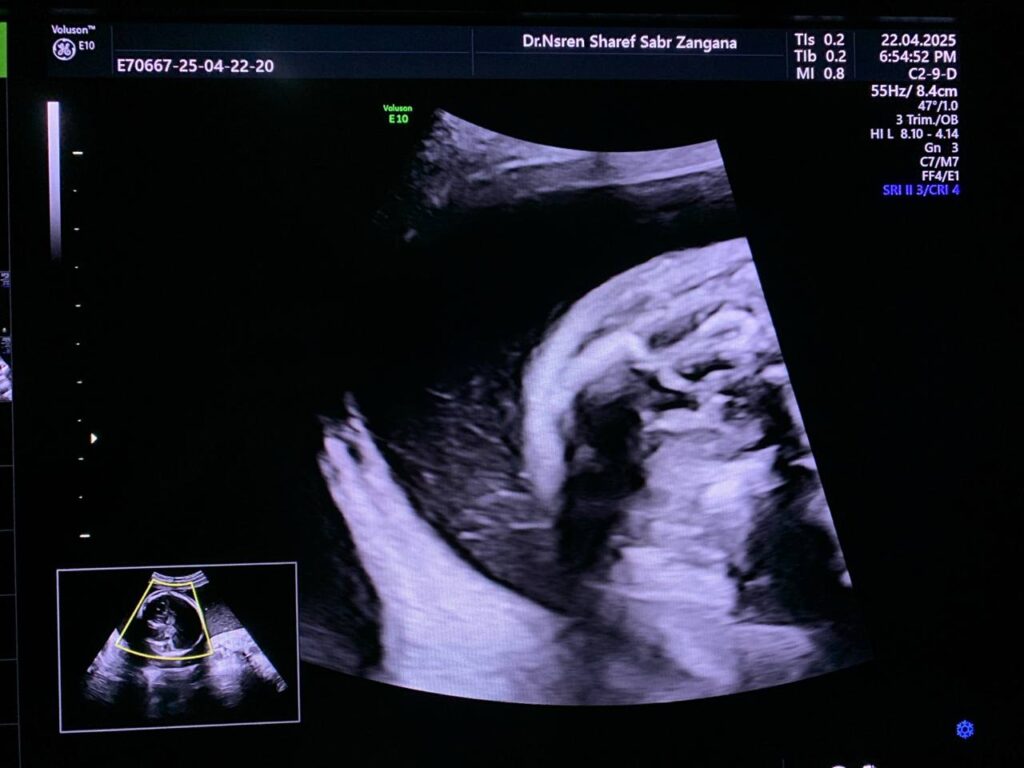

small cystic mass 9x4mm , in the posterior fossa , Blake’s pouch cyst , can not be excluded

This same patient at 26 wk